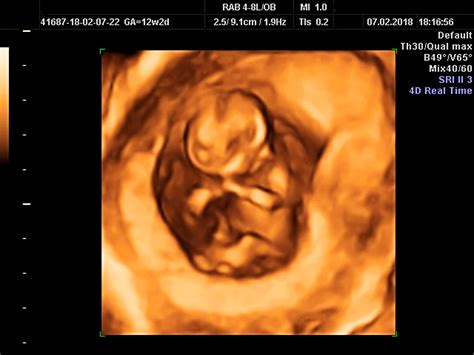

12Weeks Pregnant Ultrasound

The 12Weeks Pregnant Ultrasound is a crucial part of prenatal care. It provides valuable information about your baby's development and overall health. This ultrasound is typically performed transabdominally, meaning the ultrasound wand is moved over your belly. In some cases, a transvaginal ultrasound might be used for a clearer view, especially if you have a smaller uterus or if the baby is positioned in a way that makes it difficult to see clearly from the abdomen.

• Results: The ultrasound will provide detailed images of your baby, including measurements of the crown-to-rump length, which helps determine the gestational age. The technician will also check for the presence of a heartbeat and assess the baby's overall development.

• Crown-to-Rump Length (CRL): This measurement helps determine the baby's gestational age and overall growth. It is taken from the top of the baby's head to the bottom of the buttocks.

• Nuchal Translucency (NT) Scan: This scan measures the fluid-filled space at the back of the baby's neck. An increased measurement can indicate a higher risk of chromosomal abnormalities, such as Down syndrome. This scan is typically performed between 10 and 13 weeks.

• Heartbeat: The ultrasound will confirm the presence of a heartbeat, which is a reassuring sign of the baby's health. The heartbeat is usually visible around 6 weeks but becomes more distinct by 12 weeks.